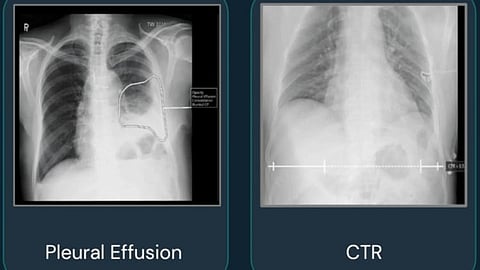

एखाद्या रुग्णाच्या फुफ्फुसाचा एक्सरे घेतल्यानंतर तो Qure Al च्या सॉफ्टवेअरवर अपलोड होतो. त्यानंतर या रुग्णाला क्षय रोग, बरगडी फॅक्चर, शरीरातील सुक्ष्मदर्शक आजार, शरीरात पाण्याची कमी असण्याचा धोका किती आहे याचा अंदाज वर्तवला जातो. रुग्णाचा अहवाल काही सेकंदात डॉक्टरना त्यांच्या मोबाईल ॲपवर मिळतो. त्यामुळे पुढील उपचार तसेच आवश्यक त्या चाचण्या घेण्यासाठीचा निर्णय लगेच घेता येतो.

डेटा हा कोणल्याही AI च्या केंद्रस्थानी असतो. हे तंत्रज्ञान विकसित करतानाही संबंधित कंपनीने फार मोठ्या प्रमाणावर मेडिकल इमेजेस वापरल्या आहेत. मेडिकल इमेजमध्ये एक्सरे, एमआरआय आदींचा समावेश होतो. या इमेजेसमधून मिळणाऱ्या डेटातून संबंधित आजरांची शक्यता वर्तवणारे मॉडेल विकसित करण्यात आले आहेत. वैद्यकीय क्षेत्रासाठी कोणतेही AI तंत्रज्ञान विकसित करताना वैद्यकीय क्षेत्रातील तज्ज्ञांचा सहभागही असतो.